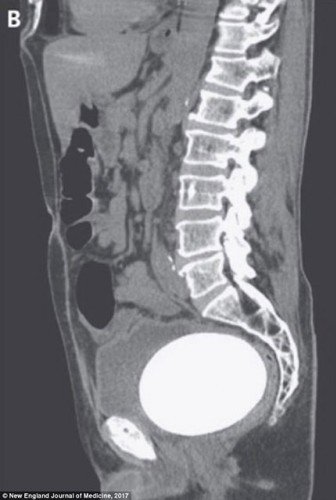

Ultrason sonuçlarına göre Amerikalı adamın idrar kesesinde 12 cm uzunluğunda, 9 buçuğa 7 buçuk cm genişliğinde bir taş vardı ve acil operasyonla alınması gerekiyordu.

Bir deve kuşu yumurtası büyüklüğünde olan mesane taşı alındıktan sonra ağırlığının 770 gram olduğu rapor edildi.